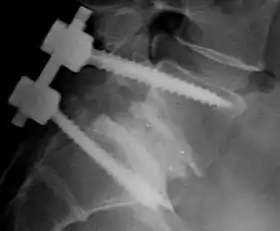

![]() Fusion of L5 and S1 | |